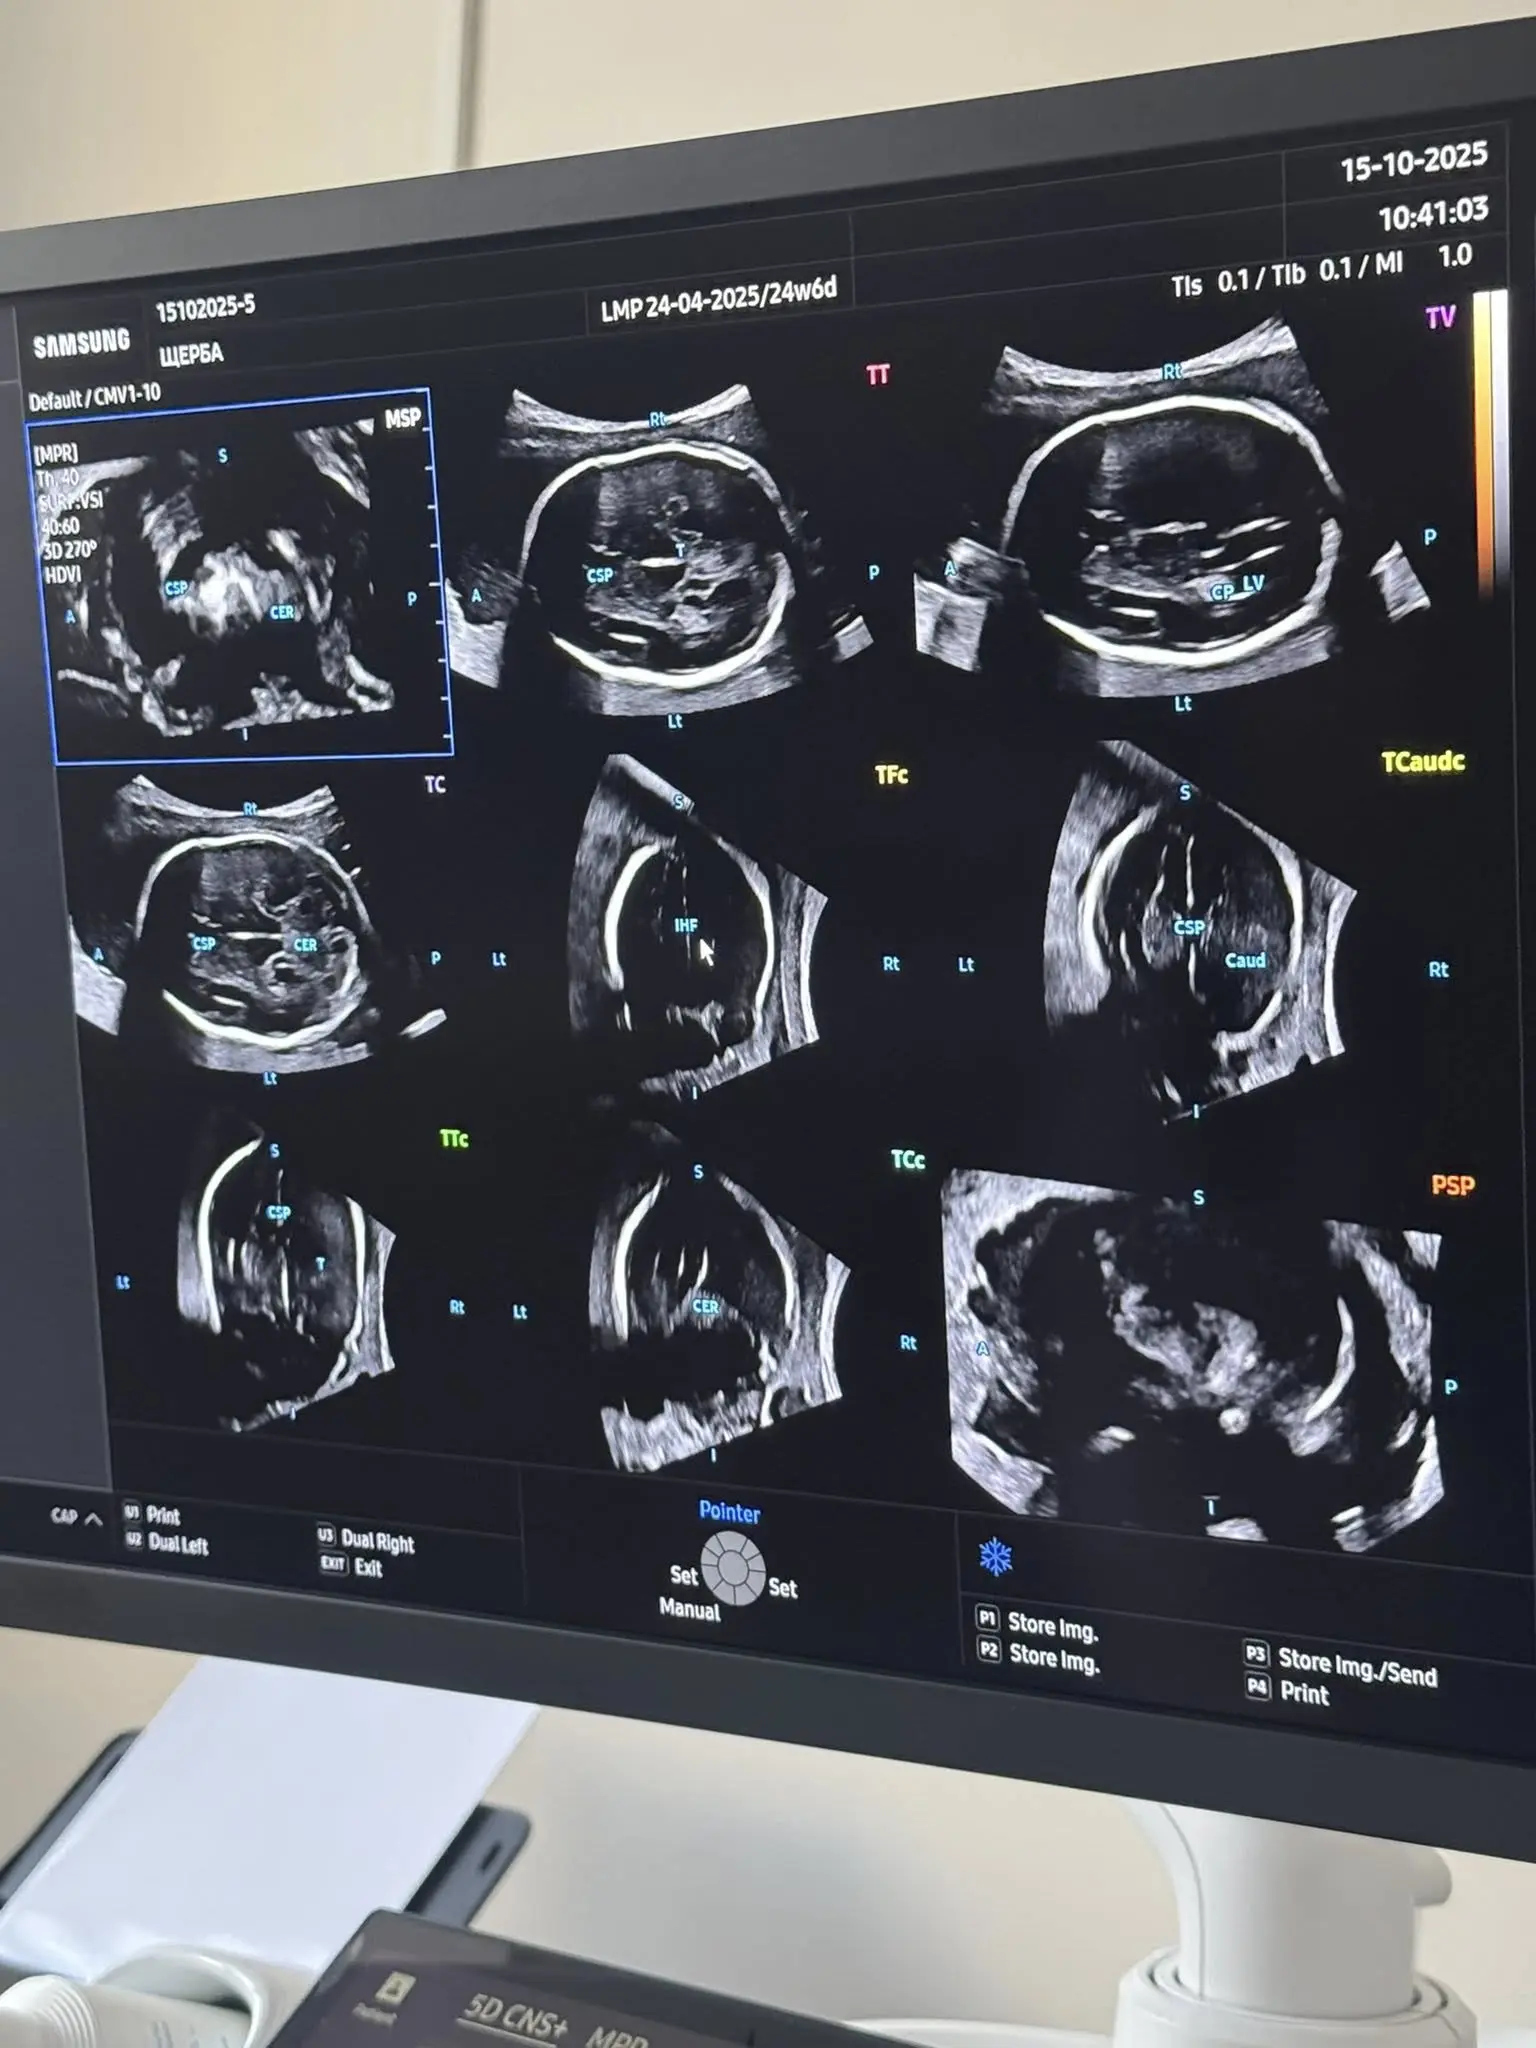

У вінницькому Центрі планування сім’ї та репродуктивного здоров’я встановили перший в Україні ультразвуковий апарат з ШІ

У Центрі планування сім’ї та репродуктивного здоров’я Вінницької обласної клінічної лікарні ім. М. І. Пирогова встановили перший в Україні ультразвуковий апарат нового покоління — Samsung HERA Z20.

Це — система експертного рівня, що поєднує штучний інтелект (AI) і 5D-візуалізацію для максимальної точності та деталізації.

HERA Z20 автоматично розпізнає анатомічні структури, проводить точні вимірювання та формує об’ємні зображення в реальному часі. А 5D Ultra Live, Crystal Architecture™ та AI ScanAssist забезпечують реалістичність — батьки можуть побачити обличчя й рухи своєї дитини ще до народження.

Зазначено, що для лікарів це можливість виявляти найменші відхилення розвитку на ранніх етапах.